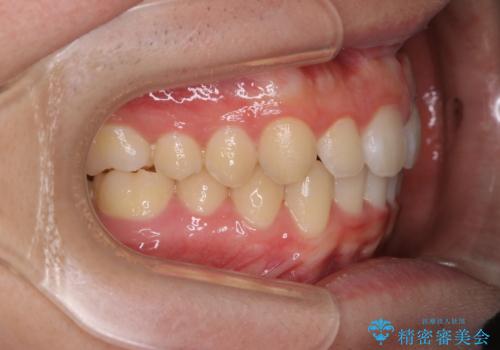

- 上の前歯が見えすぎて気になるとご相談にいらした方です。インビザラインにて前歯の圧下を行うことで歯の見え方の改善し、同時に奥歯の噛み合わせも改善を行いました。

インビザラインを正しく使用して頂けたおかげで、比較的難しいとされる歯の圧下も補助装置を使用せずに行うことが出来ました。上の前歯のラインが整ったことで笑った時の口元の印象を改善させることができ、大変喜んでいただけました。